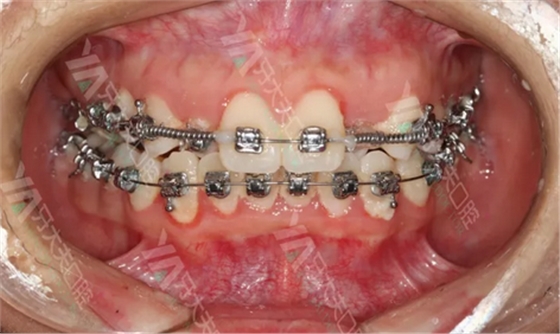

因为开学学校事情很多,我拖到第二个月才开始戴牙套(其实就是拖延症患者的强词夺理,嘻嘻嘻,图片有点小恐怖,慎点哦)

才戴牙套的那几天,连吃饭都小心翼翼,也不敢用门牙咬,心里老记着罗主任说的要用后面的牙齿吃饭。不过到后来适应了之后,就开始百无禁忌的随便吃了,哈哈哈哈。对了,戴牙套吃火锅千万别点金针菇香菜等东西!这是来自一个牙套前辈的血泪教训。